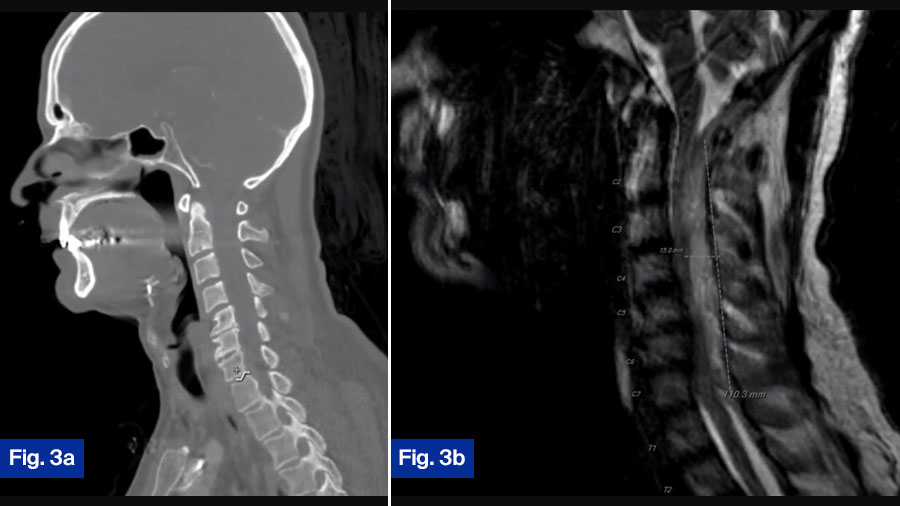

- CT scan: Showed minimal bony destruction (Figure 3a).

- MRI scan: Demonstrated a large dorsal epidural fluid collection spanning C2-T1 with substantial spinal cord compression (Figure 3b).